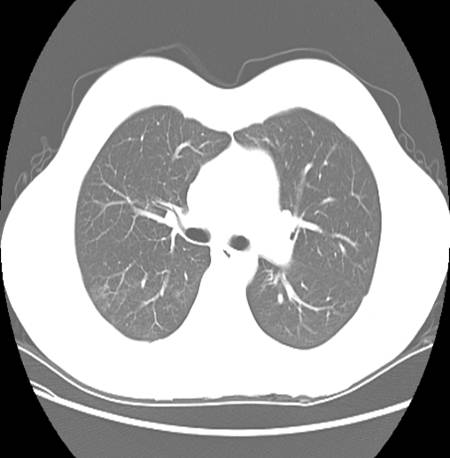

A CT chest was also ordered to further characterize the pulmonary involvement.

Describe chest CT.